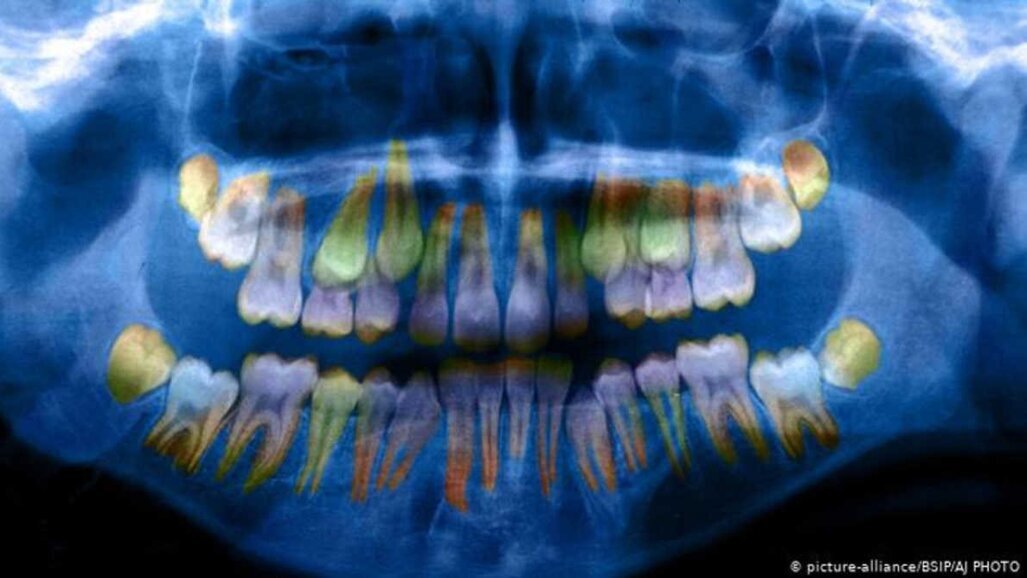

In de elementen van kinderen kan worden waargenomen of ze op jonge leeftijd zijn blootgesteld aan hoge stressfactoren. Dr. W. Thomas Boyce, hoogleraar Kindergeneeskunde en -psychiatrie aan de Universiteit van Californië presenteerde zijn bevindingen tijdens de AAAS-bijeenkomst. Volgens hem zijn de afzonderlijke lagen die het tandglazuur opbouwen dunner en minder dicht als ze worden blootgesteld aan stress, wat “de kwetsbaarheid voor cariës vergroot,” legt hij uit aan de Duitse omroep Deutsche Welle. Door een primair element in een 3D-model op basis van een röntgenfoto te onderzoeken, kan deze verandering worden gemeten.

“Maar wat we echt willen weten en wat deze snapshots niet laten zien, is de totale blootstelling aan cortisol,” voegt Boyce toe. Onderzoek naar de werkelijke tanden en kiezen kan dit aantonen, aangezien het stresshormoon de ontwikkeling van elementen beïnvloedt. De presentatie, getiteld ‘Social disparities in child oral health: Interactions between stress and pathogens’, werd gepresenteerd op 15 februari 2019 tijdens een wetenschappelijke sessie op de jaarvergadering van de AAAS.